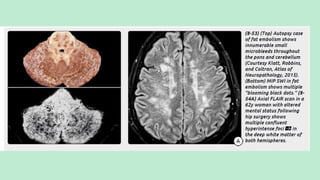

FAT EMBOLI

Hypoxia/neurological symptoms with petechial rash

in setting of severely displaced lower extremity

long bone fractures (most commonly femoral

neck fractures)

The term "cerebral fat emboli" (CFE) refers

to the neurologic manifestations of FES.

Etiology:

Small vessel occlusion from

fat particles

Inflammatory changes in

surrounding tissue initiated

by breakdown of fat into free

fatty acids and other

metabolic byproducts.

CEREBRAL FAT EMBOLI (FES)

Hallmarks is:

Arteriolar fat emboli with perivascular

microhemorrhages.

Imaging findings reflect the effects of the fat

emboli (i.e., multifocal tiny strokes and

microhemorrhages) on brain tissue, not the

fat itself.

NECT scan: Generally normal

MRI: MR shows numerous (average = 50) punctate or confluent

hyperintensities in the cerebellum, basal ganglia, periventricularWM, and GM-

WM junctions on T2/FLAIR.

DWI shows innumerable tiny punctate foci of diffusion restriction in multiple

vascular distributions, the "star field“ pattern.

The deep watershed border zones are commonly involved.

Solitary or multiple small hypointense "blooming" foci can be identified in up

to one-third of all FES cases onT2* GRE. SWI discloses innumerable (>200)

tiny "black dots" in the majority of patients.